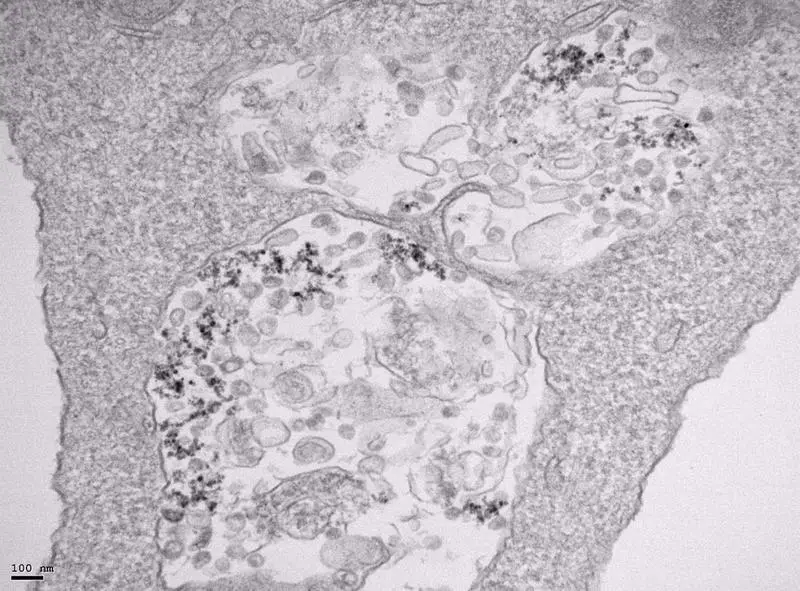

<p> Imagen de microscopía de transmisión electrónica de células infectadas con SARS-CoV-2 y tratadas con nanopartículas de óxido de hierro. - CNB-CSIC </p>

Imagen de microscopía de transmisión electrónica de células infectadas con SARS-CoV-2 y tratadas con nanopartículas de óxido de hierro. - CNB-CSIC

Domingo F. Barber, investigador del CNB-CSIC, detalla que ya se había visto que las nanopartículas de óxido se acumulan en el interior de las células en vesículas llamadas lisosomas.

"Es ahí donde con el tiempo se degradan, induciendo estrés oxidativo y alterando el metabolismo intracelular del hierro. Dado que el estrés oxidativo afecta a la estabilidad de la membrana lipídica del virus de la gripe y reduce su capacidad de infección, pensamos que podría ocurrir lo mismo con el SARS-CoV-2 y decidimos tratar células infectadas con SARS-CoV-2 con diferentes tipos de nanopartículas, unas producidas por el grupo del ICMM-CSIC y otras comerciales, como son un antianémico y un agente de contraste de resonancia magnética", indica Barber.